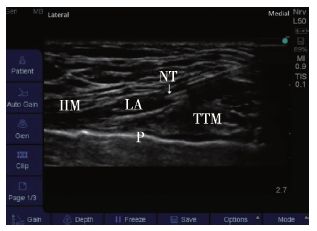

2015年Ueshima等首先描述了TTMP阻滞(图2),主要用于阻滞肋间神经前皮支。操作方法为超声引导下将局麻药物从胸骨旁注射到胸横肌上方。Ueshima等发现Pecs阻滞复合TTMP比单纯Pecs阻滞更能减少乳腺癌手术后疼痛并减少阿片类药物的使用。

图2 胸横肌解剖声像图。注:NT,穿刺针针尖;LA,局麻药物;IIM,肋间内肌;TTM,胸横肌